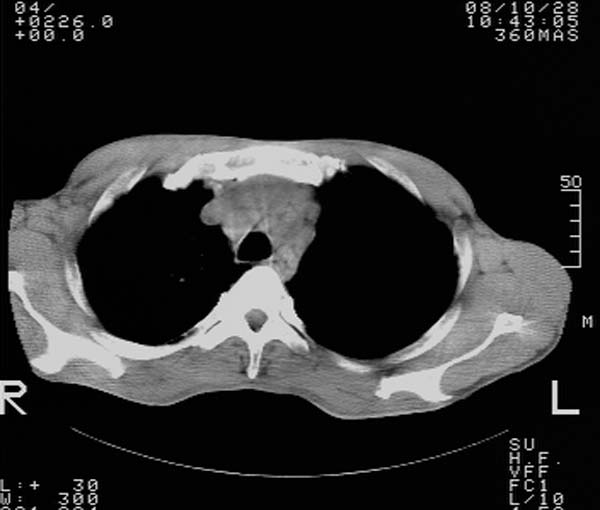

m,65y。半年前发现颈小结节,逐渐增多增大,现双侧耳后、颌下及颈部表浅淋巴肿大。胸片示双肺门增大。外院曾穿刺诊断为淋巴结核。在我科作胸腹部ct,我们觉得外院病检有误。现将图像上传请战友讨论。

纵隔内及腹膜后广泛淋巴结肿大,脾大,肝内似可见低密度影,结合病史半年前发现颈小结节,逐渐增多增大,现双侧耳后、颌下及颈部表浅淋巴肿大。考虑淋巴瘤。

纵隔,双肺门腹膜后多发淋巴结重大,非融合,肝脾轻度肿大,双肺野弥漫性小结节;考虑淋巴瘤,结节病可能性

纵隔内,双肺门、腋窝及腹膜后多发肿大淋巴结影,肺内小结节影,肝脾体积增大,支持淋巴瘤。肝内多发低密度影,考虑小囊肿。

纵隔内,双肺门、腹膜后多发肿大淋巴结影及颈部淋巴结肿大,肝脾体积大.结合临床,淋巴瘤可能性大。